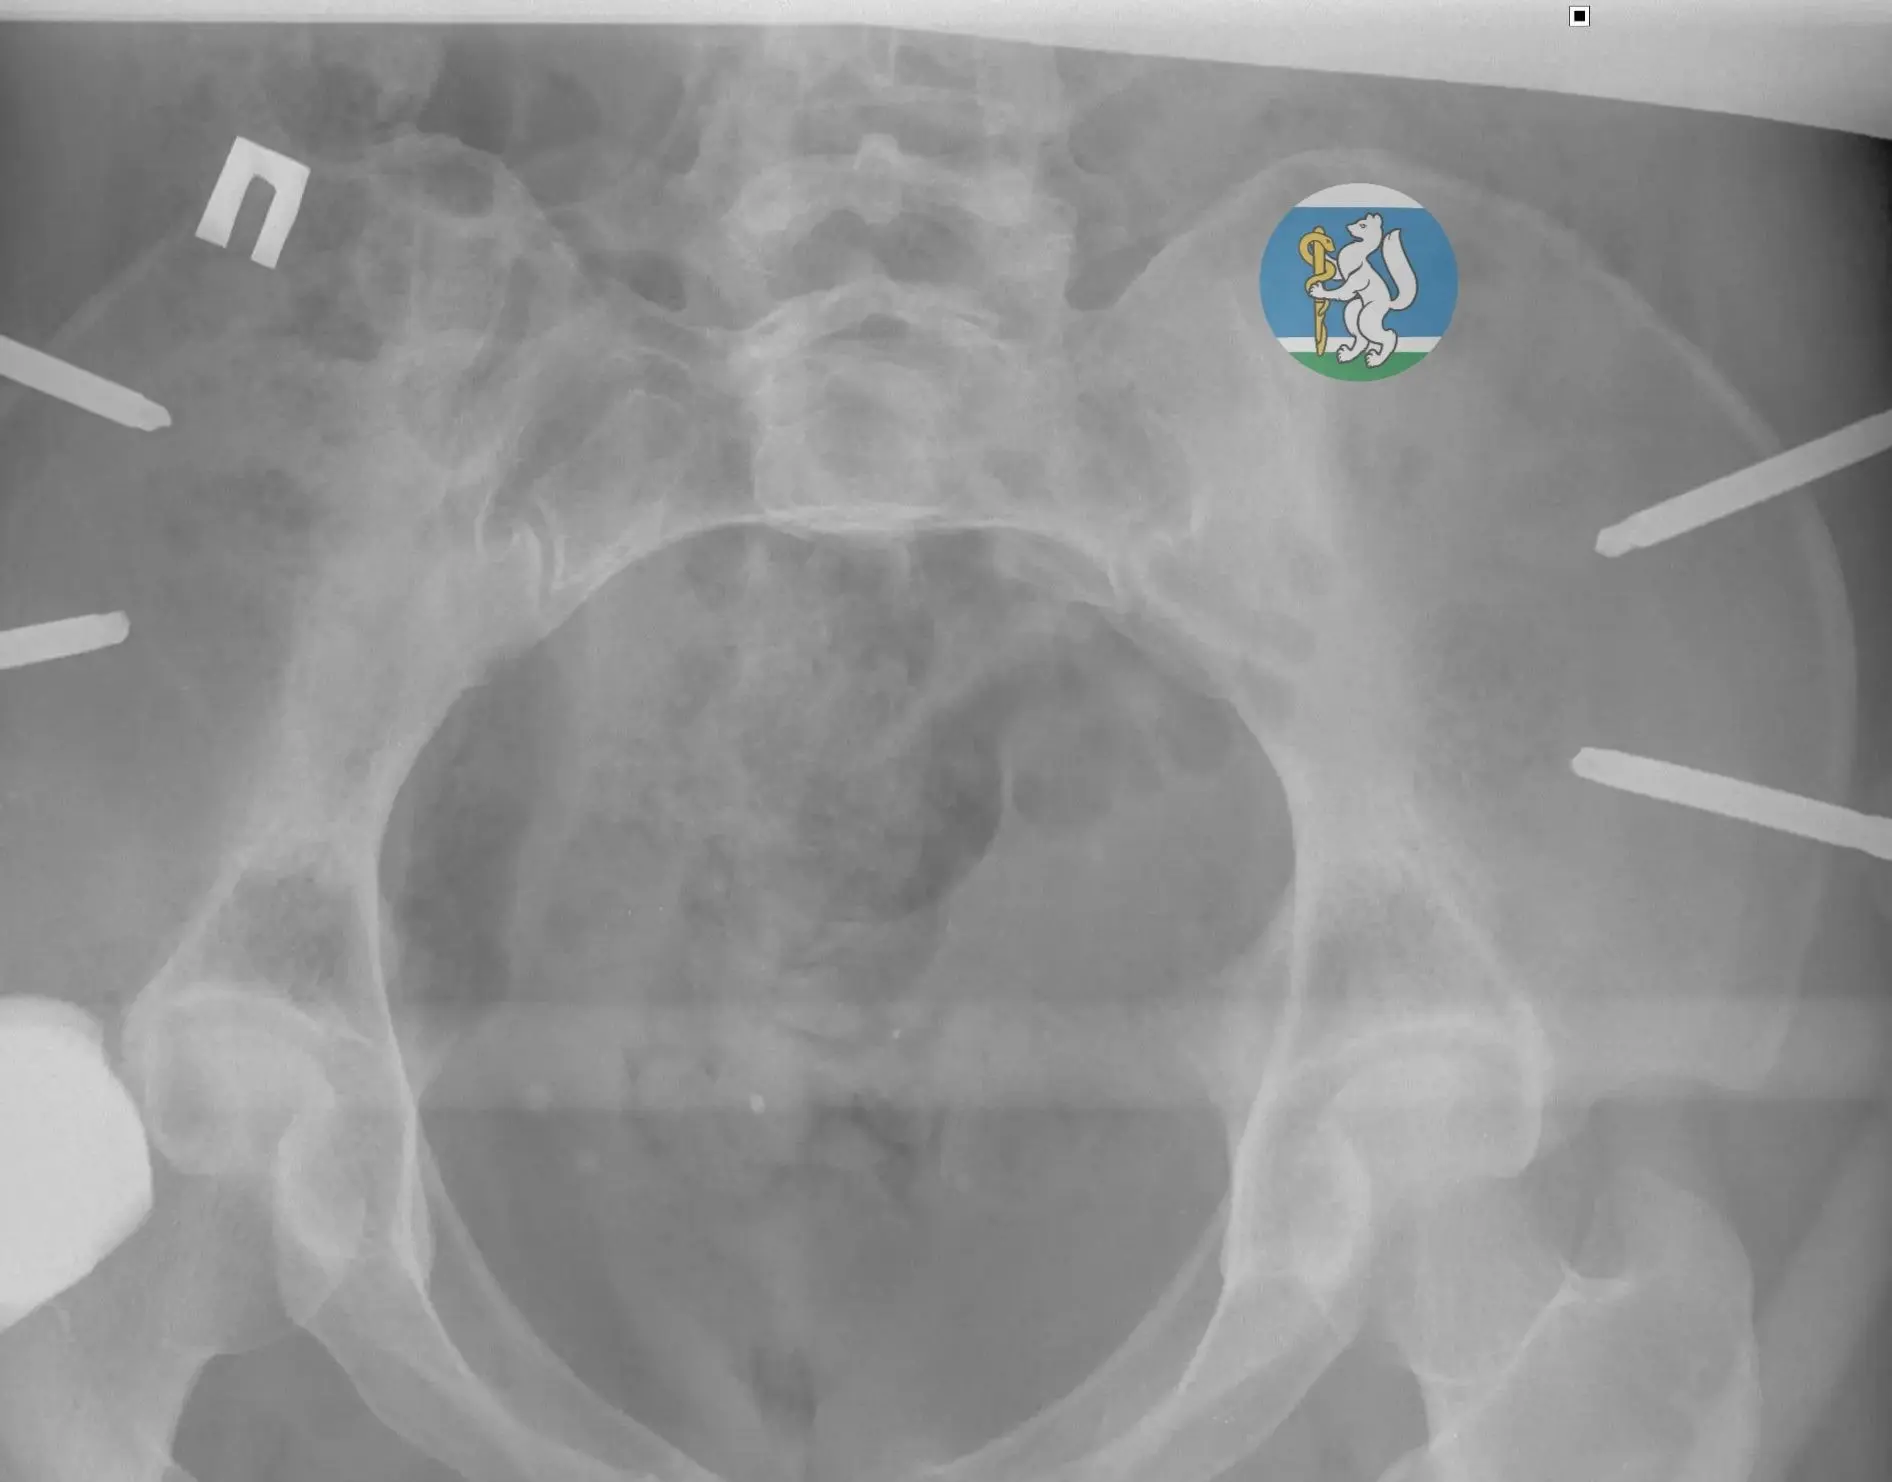

🎥 14 друзей спасают человека, который выиграл джекпот.

Только не друзей, а врачей, и "джекпот" состоит из рака печени и тромба в сердце.

❗️ Мультидисциплинарная команда специалистов Свердловской областной клинической больницы №1 успешно прооперировала 23-летнего екатеринбуржца с фиброламеллярной карциномой – редкой формой рака печени, которая была осложнена опухолевым тромбом, распространившимся по нижней полой вене вплоть до правого предсердия.

🚑 До ноября 2025 года 23-летний житель Екатеринбурга не жаловался на здоровье и ни разу не лежал в больнице. Внезапно у него появились тошнота и сильная боль в подреберье слева. В Городской клинической больнице №40 у пациента на УЗИ выявили опухоль печени, а в Свердловском областном онкологическом диспансере диагностировали её как редкую форму рака — фиброламеллярную карциному.

«Фиброламеллярная карцинома устойчива к большинству противоопухолевых препаратов. Продолжительность жизни пациентов без операции редко превышает один год».

Единственный шанс на спасение в такой ситуации — сложная операция, во время которой необходимо одновременно удалить поражённую заболеванием часть печени и избавиться от опухолевого тромба.

😱Сложнейшее вмешательство, которое продолжалось 11 часов, выполнила операционная бригада, в состав которой вошли 14 специалистов СОКБ №1. Имена этих героев и описание уникальной операции читайте в нашем материале.